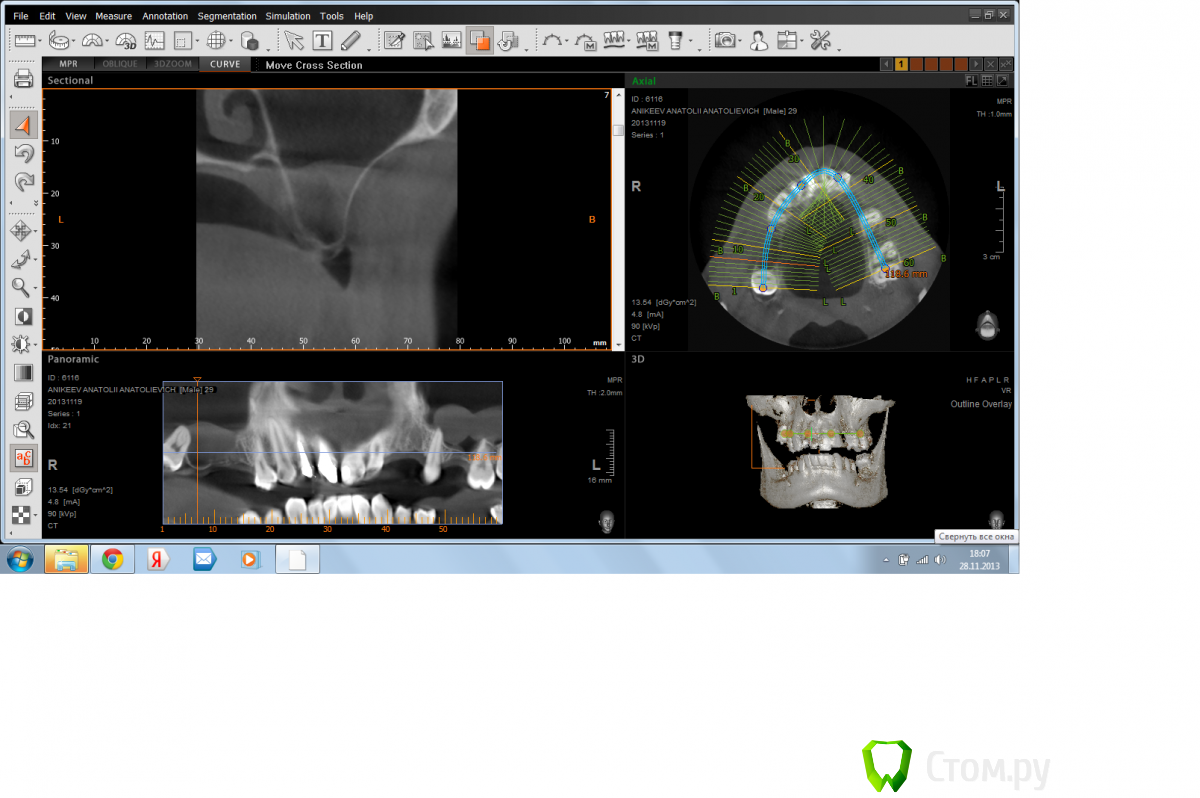

Doctorstomlis Опубликовано 29 ноября, 2013 Поделиться Опубликовано 29 ноября, 2013 Здравствуйте!У меня что-то подобное.Как Вы думаете,какова здесь тактика(я имею ввиду патологию в гайморовой пазухе) Ссылка на комментарий

ВИТА Опубликовано 31 января, 2014 Поделиться Опубликовано 31 января, 2014 Здравствуйте!У меня что-то подобное.Как Вы думаете,какова здесь тактика(я имею ввиду патологию в гайморовой пазухе)я бы сделала откр синус лифт аккуратно....по видимому это гипертрофия слизистой, подниматься даже лучше будет из-за своей плотности Ссылка на комментарий

Елена777 Опубликовано 1 февраля, 2014 Поделиться Опубликовано 1 февраля, 2014 Если клиники нет, я бы делала открыт синус. Ссылка на комментарий